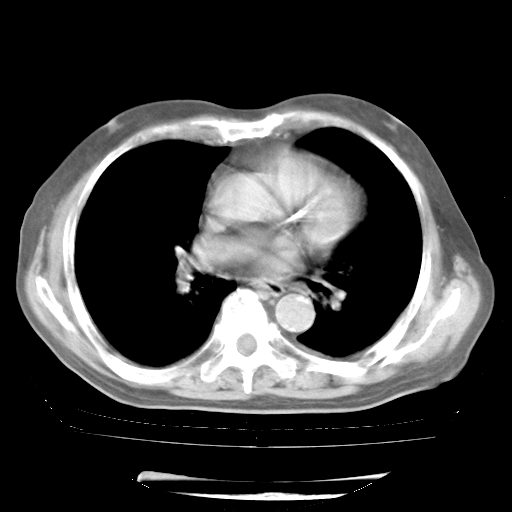

4月28日肺部CT——再次出现类似去年5月9日——透光度降低,“间质性”改变。

4月28日肺部CT——再次出现类似去年5月9日——磨玻璃样、间有“粟粒样”改变。